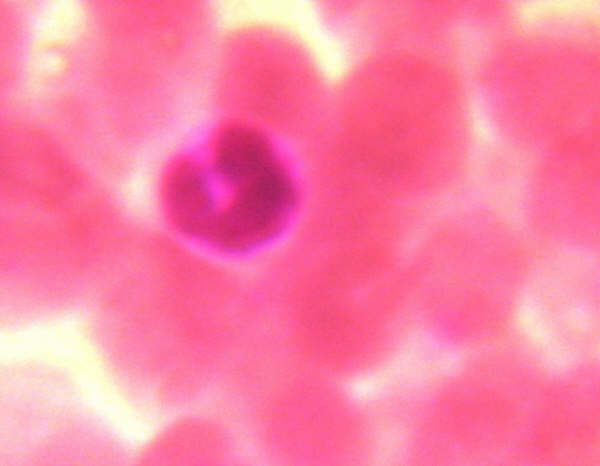

2) Con otra portaobjetos limpio se extienden las gotas de sangre. Se le añade alcohol para fijar la práctica y se le añade Violeta de Genciana durante cinco minutos. Se lava y se vuelve a dejar secar.

3) Se le añade un cubreobjetos y observaremos los glóbulos blancos.

Algunas observaciones realizadas por nuestros alumnos han sido las siguientes: